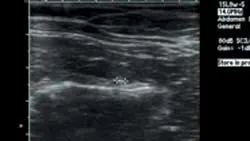

Static left renal disease and mild hydronephrosis of the right kidney with proximal hydroureter were evident on renal ultrasonography (Figure 3, right: Ultrasound of the right kidney showing pelvic dilation. View larger image). Renal calculi were present bilaterally.

Repeat ultrasonography and right-sided pyelocentesis with contrast confirmed right-sided hydronephrosis and hydroureter with no contrast progressing into the urinary bladder (Figure 4, above: Pyelogram identifying hydronephrosis of the right kidney and proximal hydroureter. Contrast material does not progress into the urinary bladder. View larger image). A ureterolith associated with the hydroureter was also visualized (Figure 5, below: Ultrasound identifying dilation of the right ureter associated with a ureterolith. View larger image).